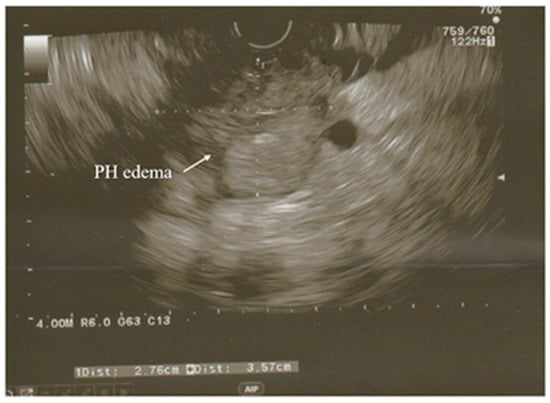

3.3. Ultrasonography

- Sirli, R.; Sporea, I. Ultrasound examination of the normal pancreas. Med. Ultrason. 2010, 12, 62–65. [Google Scholar]

- Rizk, M.K.; Gerke, H. Utility of endoscopic ultrasound in pancreatitis: A review. World J. Gastroenterol. 2007, 13, 6321. [Google Scholar] [CrossRef]

- Kotwal, V.; Talukdar, R.; Levy, M.; Vege, S.S. Role of endoscopic ultrasound during hospitalization for acute pancreatitis. World J. Gastroenterol. 2010, 16, 4888. [Google Scholar] [CrossRef]